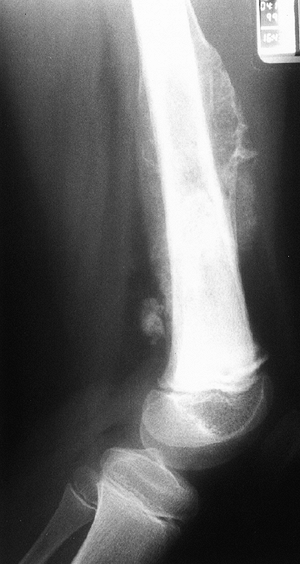

![]() |

Figure 14.7

Anteroposterior plain radiograph of an 18-year-old man with an osteosarcoma of his proximal tibia. There is increased density in the proximal tibia associated with cortical destruction and extraosseous bone formation. Biopsy was confirmatory. |